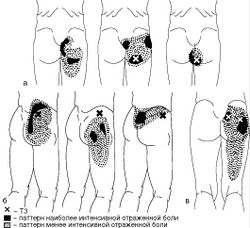

- Боль в не менее чем 11 из 18 парных двусторонних «чувствительных» зон, определенных в качестве диагностически значимых Американским колледжем ревматологов, при пальпации с давлением примерно в 4 кг (или до побледнения ногтевых пластинок) (Рис. 13):

- на затылке в месте прикрепления подзатылочных мышц;

- в области между поперечными отростками СV-СVII;

- посередине верхнего края трапециевидной мышцы;

- над лопаточной остью у медиального края лопатки;

- у второго грудинно-реберного сочленения;

- на 2 см дистальнее латерального надмыщелка плеча;

- вверху верхнелатерального квадранта ягодиц;

- позади большого вертела;

- на медиальной поверхности коленного сустава проксимальнее суставной щели.